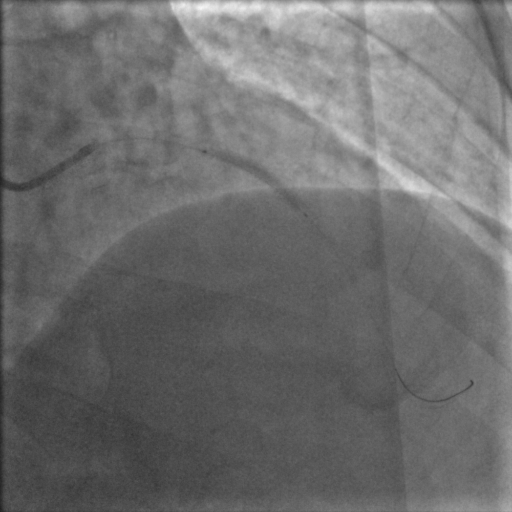

Coronary angiography was done through right radial access which demonstrated severe Instent restenosis (ISR) in the mid portion of LAD stent. LCX and RCA were normal.